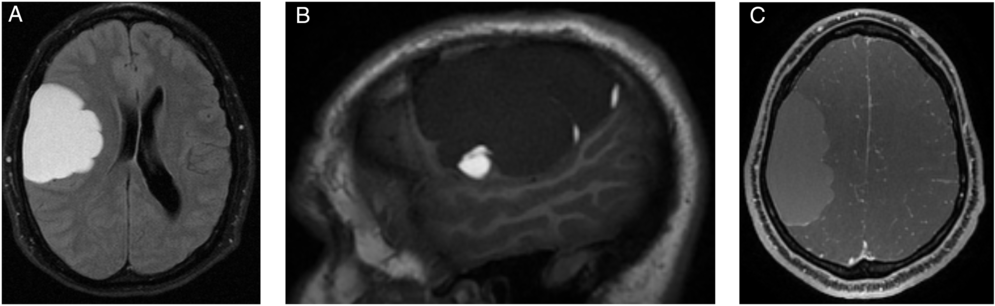

This is a case of a 30-year-old right-handed male patient who presented to the hospital in 2014 after hitting his head on the mat during a wrestling match followed by headache and temporary peripheral vision limitation. The patient’s past medical history was unremarkable. On physical examination, Glasgow Coma Scale was 15 with no focal neurological deficits. Unenhanced head computed tomography (CT) and enhanced brain magnetic resonance imaging (MRI) were performed (Figure 1). The patient was managed conservatively, and follow-up CT and MRI in 2015 (Figure 2) demonstrated significant decrease in size of the previously seen right frontoparietal lesion with also changes in its radiological features. The patient remained asymptomatic for about 3 years when in 2018 he presented to the Emergency Department with increasing headaches and peripheral vision loss. MRI demonstrated an increase in the right frontal lesion size (Figure 3). He underwent surgical resection of the lesion.

Figure 3: Follow-up MRI after 3 years when the patient became symptomatic: Axial FLAIR (A) demonstrates an increase in size of the cystic lesion. On sagittal T1-weighted images (B), the content of lesion became hypointense with some remaining areas of increased signal in the periphery of the lesion. Axial T1 postcontrast showed areas of minimal linear enhancement (C).